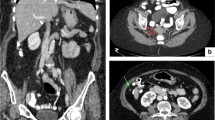

All eligible patients underwent CT in the supine position with intravenous and oral contrast. Digital CT images were obtained by convention reformatted in the coronal and sagittal planes. CT-PCI was retrospectively scored using the Sugarbaker classification [20] by one of two radiology specialists (HS or JB). The CT-PCI was calculated as the sum of the numerical lesion scores assigned to the 13 abdominopelvic regions and the lesion score to the largest visible implant. Ascites (three groups) was estimated by one of two radiologists (HS or JB) concurrent with the CT-PCI evaluation. CT-ascites was evaluated qualitatively by the interpreting radiologist and assigned to one of three groups (< 500 ml, 500–1000 ml, and > 1000 ml). The CT-ascites evaluation was based on all three image projections. CPLNs were retrospectively assessed by one of two radiology specialists (SP or NOW). CPLN was defined as a pathological enlargement measuring ≥ 5 mm at the short axis in the axial plane and was scored as negative (i.e., normal) or positive (i.e., enlarged) by two radiologists (NOW and SP). The radiologists were blinded to the intraoperative data and surgical outcomes (Fig. 1).

Peritoneal carcinomatosis and ascites in patients with ovarian cancer. a CT-image (contrast-enhanced CT of the abdomen and pelvis, coronary projection) showing right diaphragmatic carcinomatosis, left-side pervic carcinomatosis, and pelvic masses. b CT-image (intravenous and oral-enhanced CT of the abdomen and pelvis, coronary projection) carcinomatosis in truncus coeliacus area

Linear regression analysis revealed a positive correlation between increasing CT-PCI and the S-PCI (both continuous data) (0.511 (95% CI 0.387–0.639), p < 0.001) (Fig. 2). Statistical significance was maintained when the data were adjusted for CA-125 level, ascites and time between the CT scan and surgery (0.397 (95% CI 0.252–0.541) p < 0.001)) (Table 2).

When the results were adjusted for CA-125 level, CPLNs, ascites, and days between the CT scan and surgery, the association was still significant (OR 1.069 (1.009–1.132), p < 0.023) (Table 3). The results were confirmed by ROC analyses, with an AUC of 0.715 (95% CI 0.609–0.822, p = 0.000) and generating a cut-off value of 21 for CT-PCI (Fig. 3). The sensitivity, specificity, positive predictive value and negative predictive value were 58.5% (CI 42.1–73.7%), 70.3% (CI 58.5–80.3%), 52.2% CI 41.3–62.7%) and 75.4% (CI 67.4–81.9%), respectively. The accuracy for CT-PCI ≥ 21 was 66.1% (56.67–74.65%).